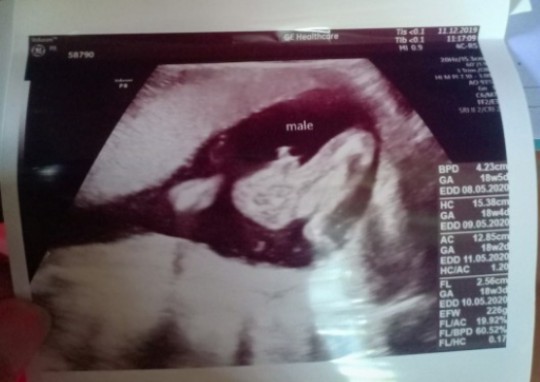

บ้านนี้ 17 พ.ค ลูกชายจ้า